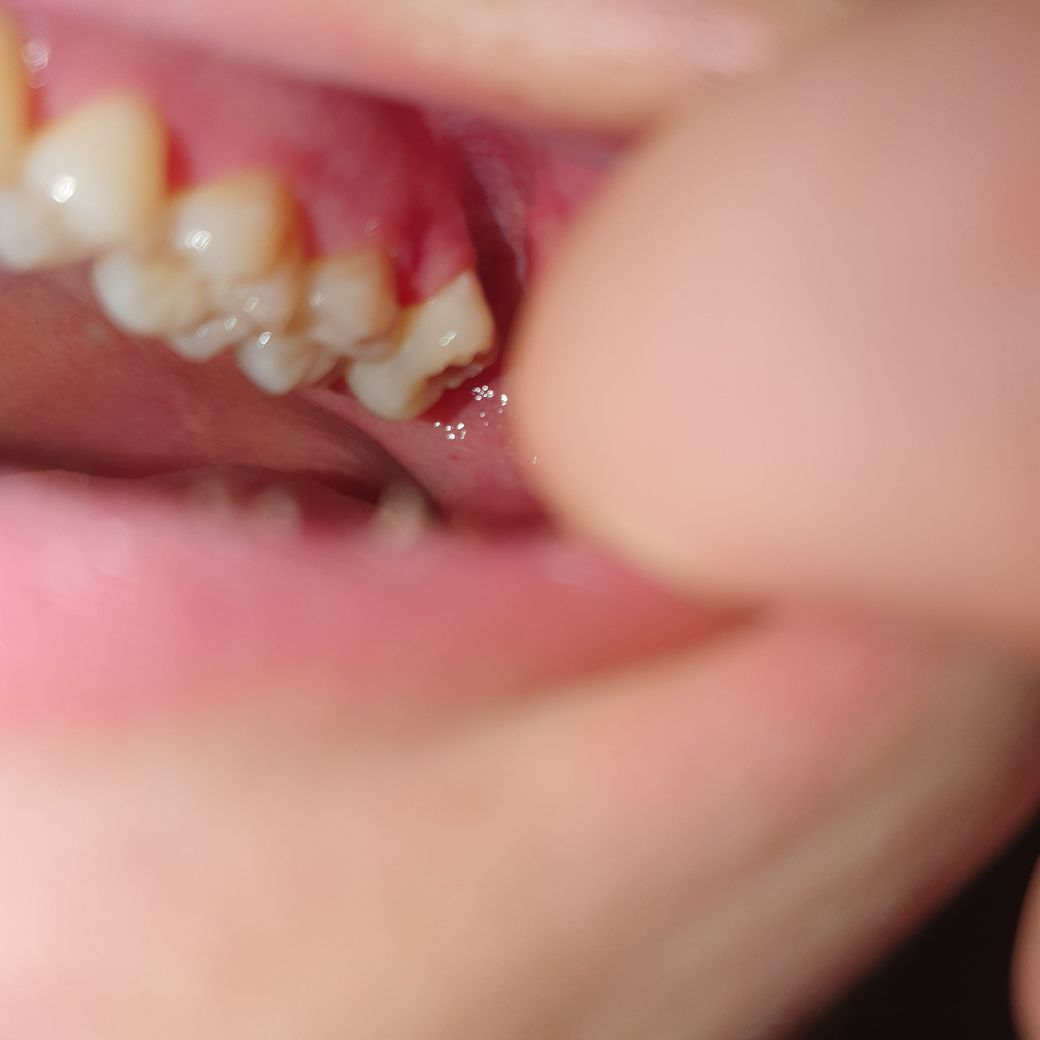

저기는 나름 다 나와있는거 같은데 혹시 이런 경우에 마취 안하고 뽑는 경우도 있나요?

그런 글들을 본거 같아서요.. 뭔가 무서운데

이것도 마취하고 뽑겠죠? 그리고 사랑니 뽑고나서 반대쪽 사랑니는

당연히 마취를 해야됩니다. 마취를 하지 않고는 발치를 하실수 없으며 위쪽은 잘 꼬매지는 않습니다.

마취는 하고 뽑습니다. 마취 없이 발치를 하는 경우는 없습니다. 바로 발치하는 것도 가능합니다.

사랑니 발치시 마취하고 뽑습니다.